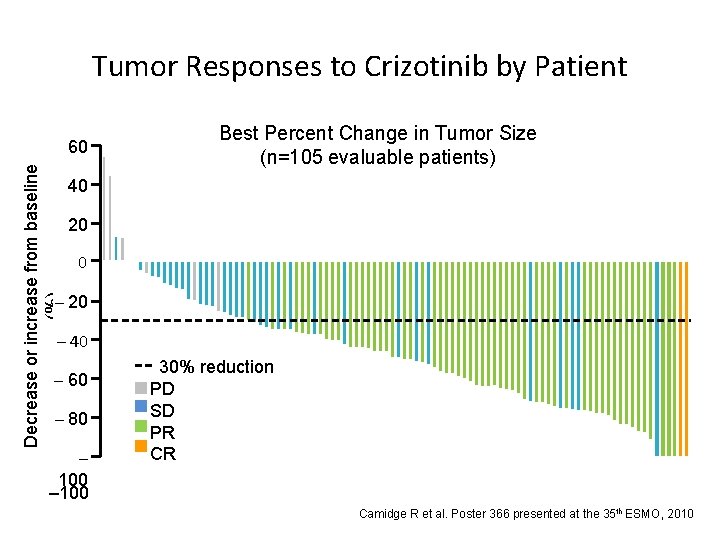

Decrease or increase from baseline (%) Tumor Responses to Crizotinib by Patient 60 50 40 Best Percent Change in Tumor Size (n=105 evaluable patients) 20 20 0 –– 10 20 – 40 – 60 –– 70 80 – 100 30% reduction PD SD PR CR Camidge R et al. Poster 366 presented at the 35 th ESMO, 2010

Decrease or increase from baseline (%) Tumor Responses to Crizotinib by Patient 60 50 40 Best Percent Change in Tumor Size (n=105 evaluable patients) 20 20 0 –– 10 20 – 40 – 60 –– 70 80 – 100 30% reduction PD SD PR CR Camidge R et al. Poster 366 presented at the 35 th ESMO, 2010